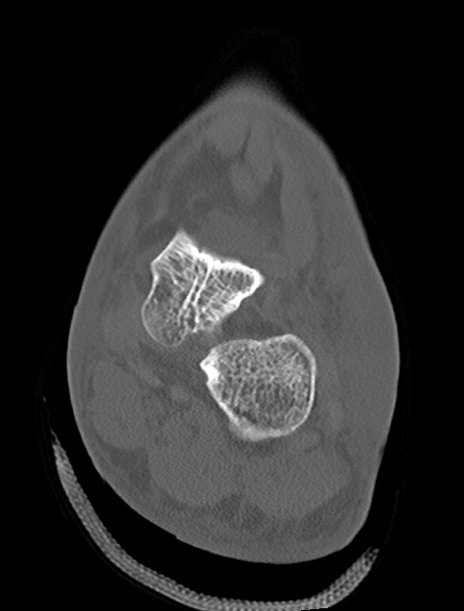

左足関節CT

横断像